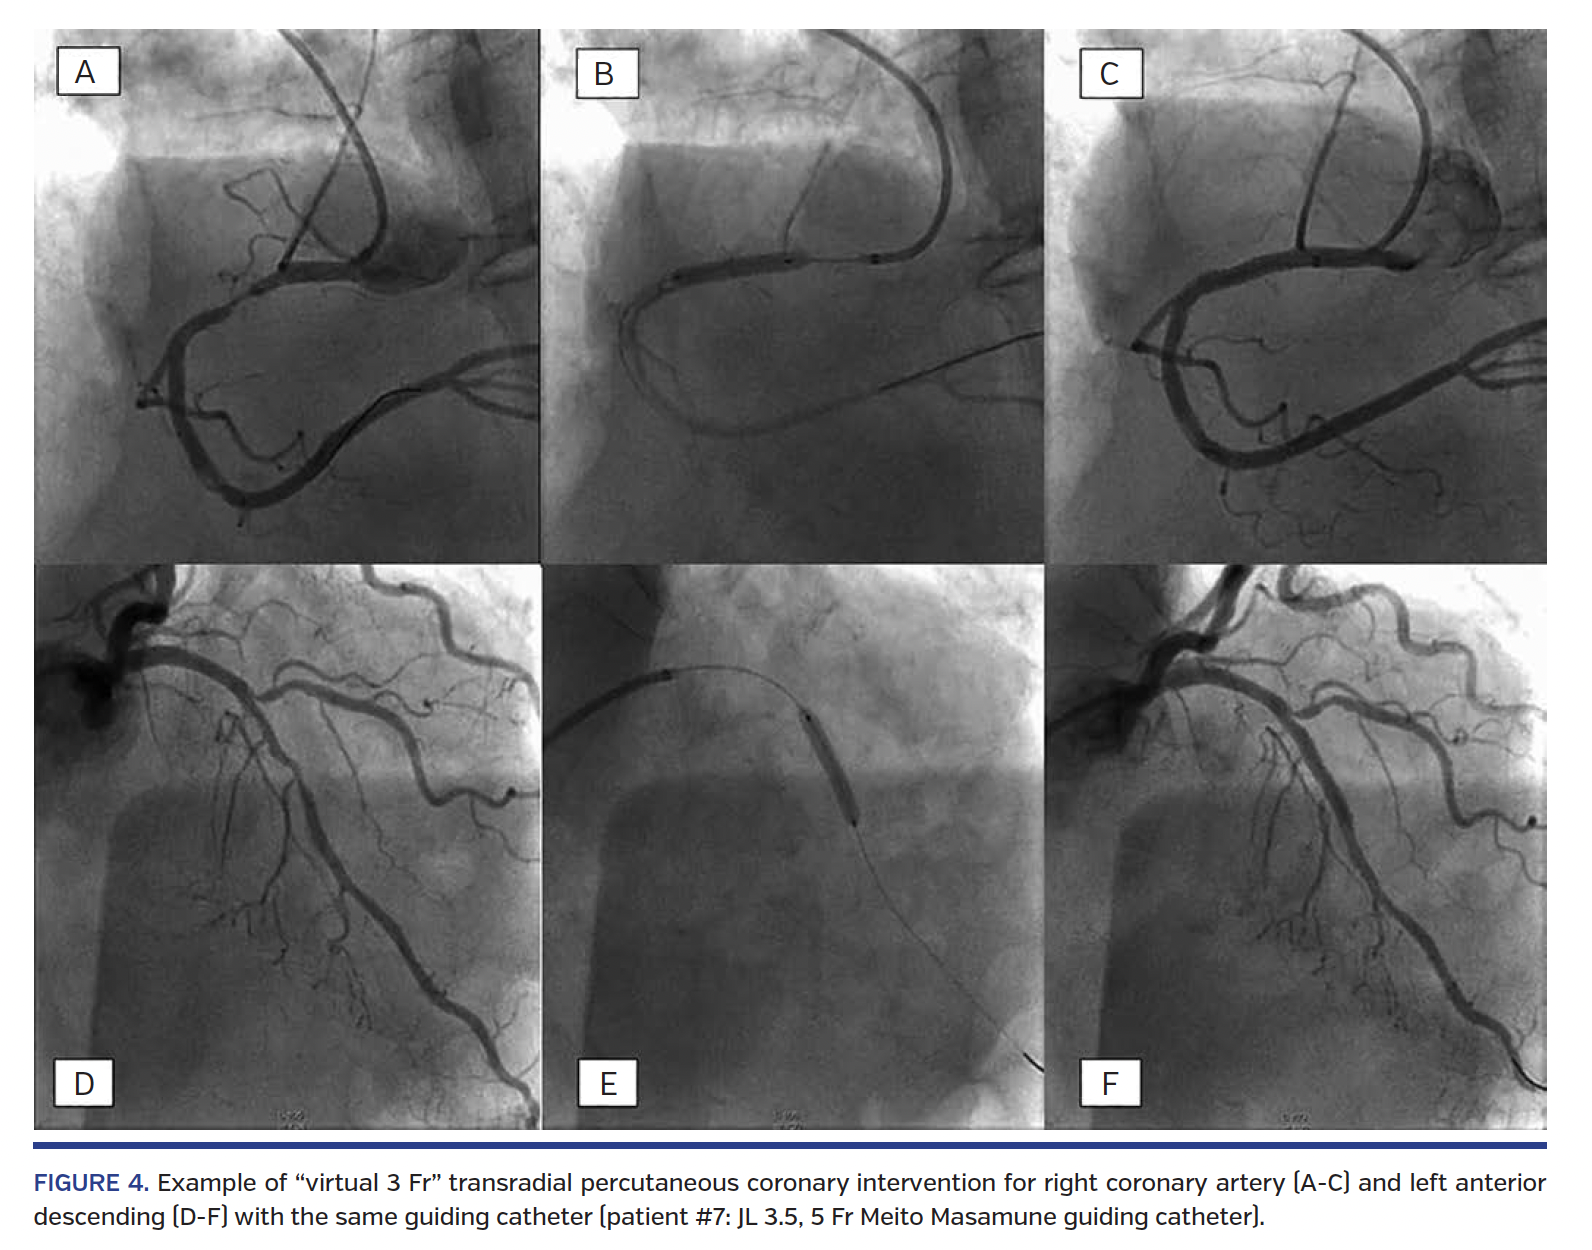

In 10 out of 11 patients, the procedure was successfully accomplished with a 5 Fr Meito-Masamune guiding catheter, and in 3 out of 10 patients the same guiding catheter was used for engaging both the left and right coronary artery (Multipurpose once, JL 3.5 twice) (Figure 4).

In cases of multivessel PCI of both the right and left coronaries, cannulation of both ostia is sought with the same catheter; during manipulation of the catheter, the inner dilator is reinserted (without extruding from the tip of the catheter) in order to confer extra support to the system.